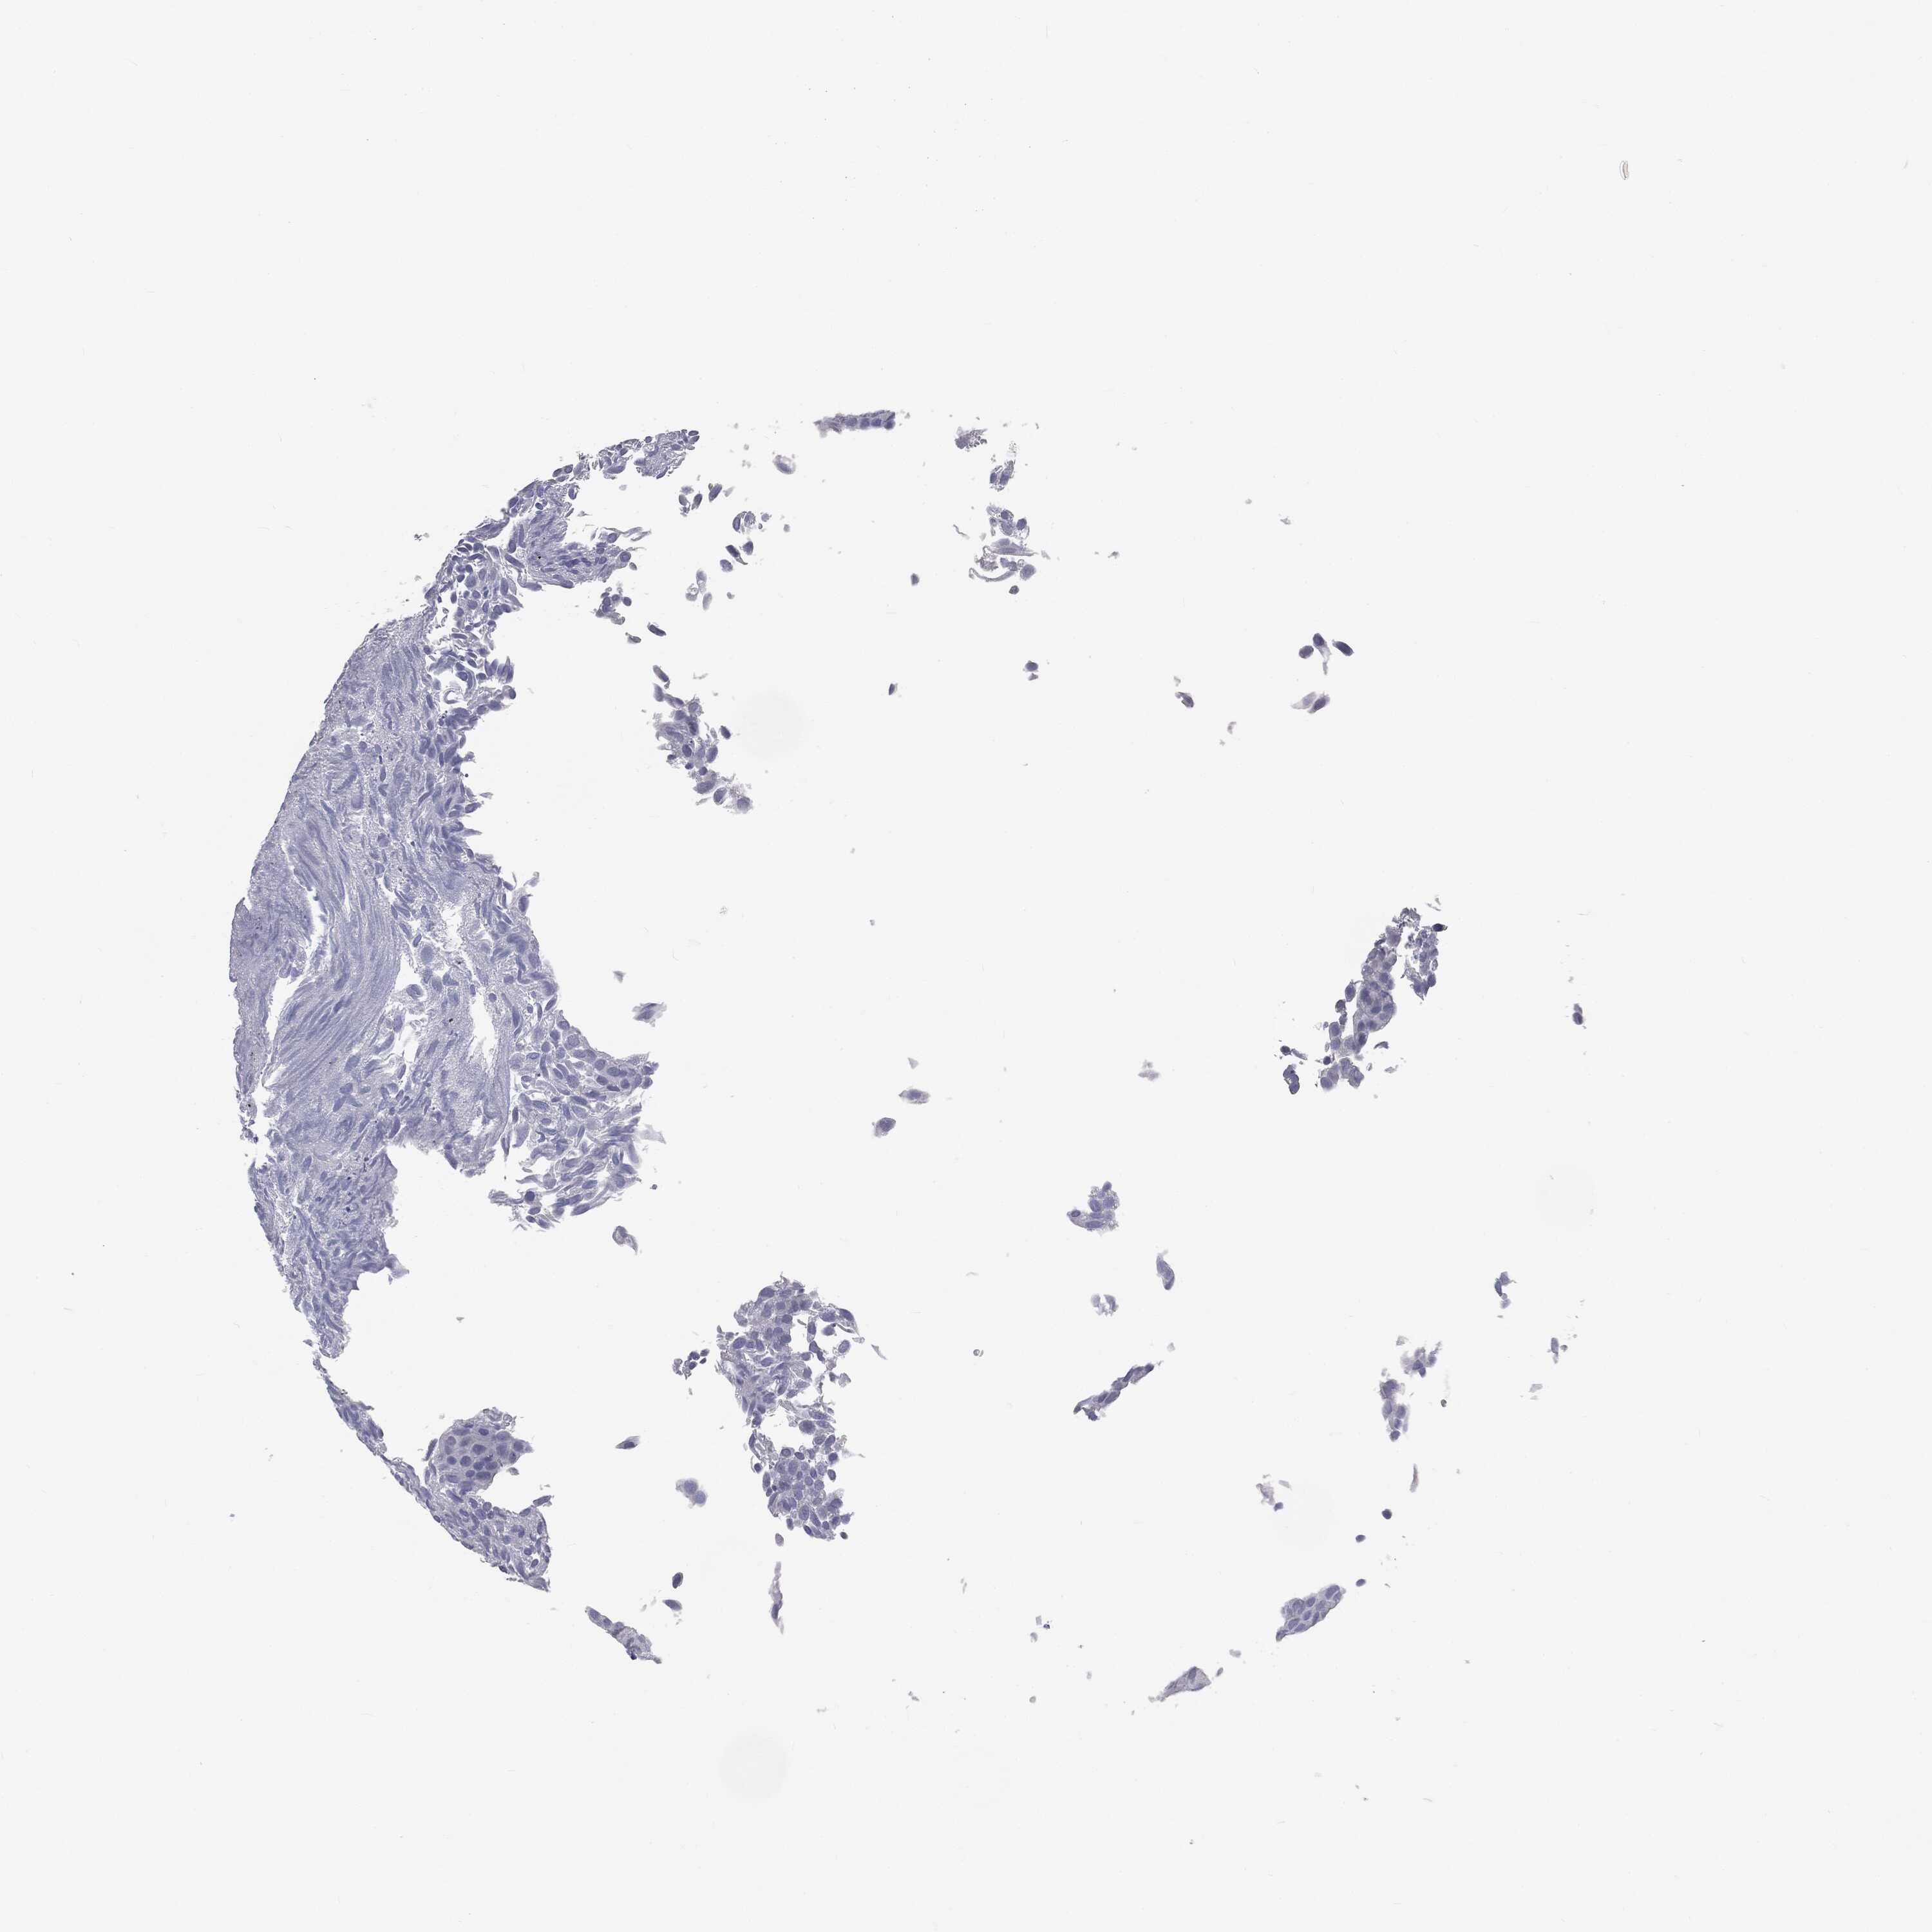

UROTHELIAL CANCER - Protein expressioni

A mouse-over function shows sample information and annotation data. Click on an image to view it in a full screen mode. Samples can be filtered based on level of antibody staining by selecting one or several of the following categories: high, medium, low and not detected. The assay and annotation is described here.

Antibody stainingi

Antibody staining in the annotated cell types in the current human tissue is reported as not detected, low, medium, or high, based on conventional immunohistochemistry profiling in selected tissues. This score is based on the combination of the staining intensity and fraction of stained cells.

Each image is clickable and will lead to virtual microscopy that enables deeper exploration of all samples and also displays staining intensity scores, fraction scores and subcellular localization as well as patient and tissue information for each sample.

Antibody HPA045153

Antibody CAB080138

Urothelial carcinoma, High grade

Urothelial carcinoma, NOS

Urothelial carcinoma, Low grade